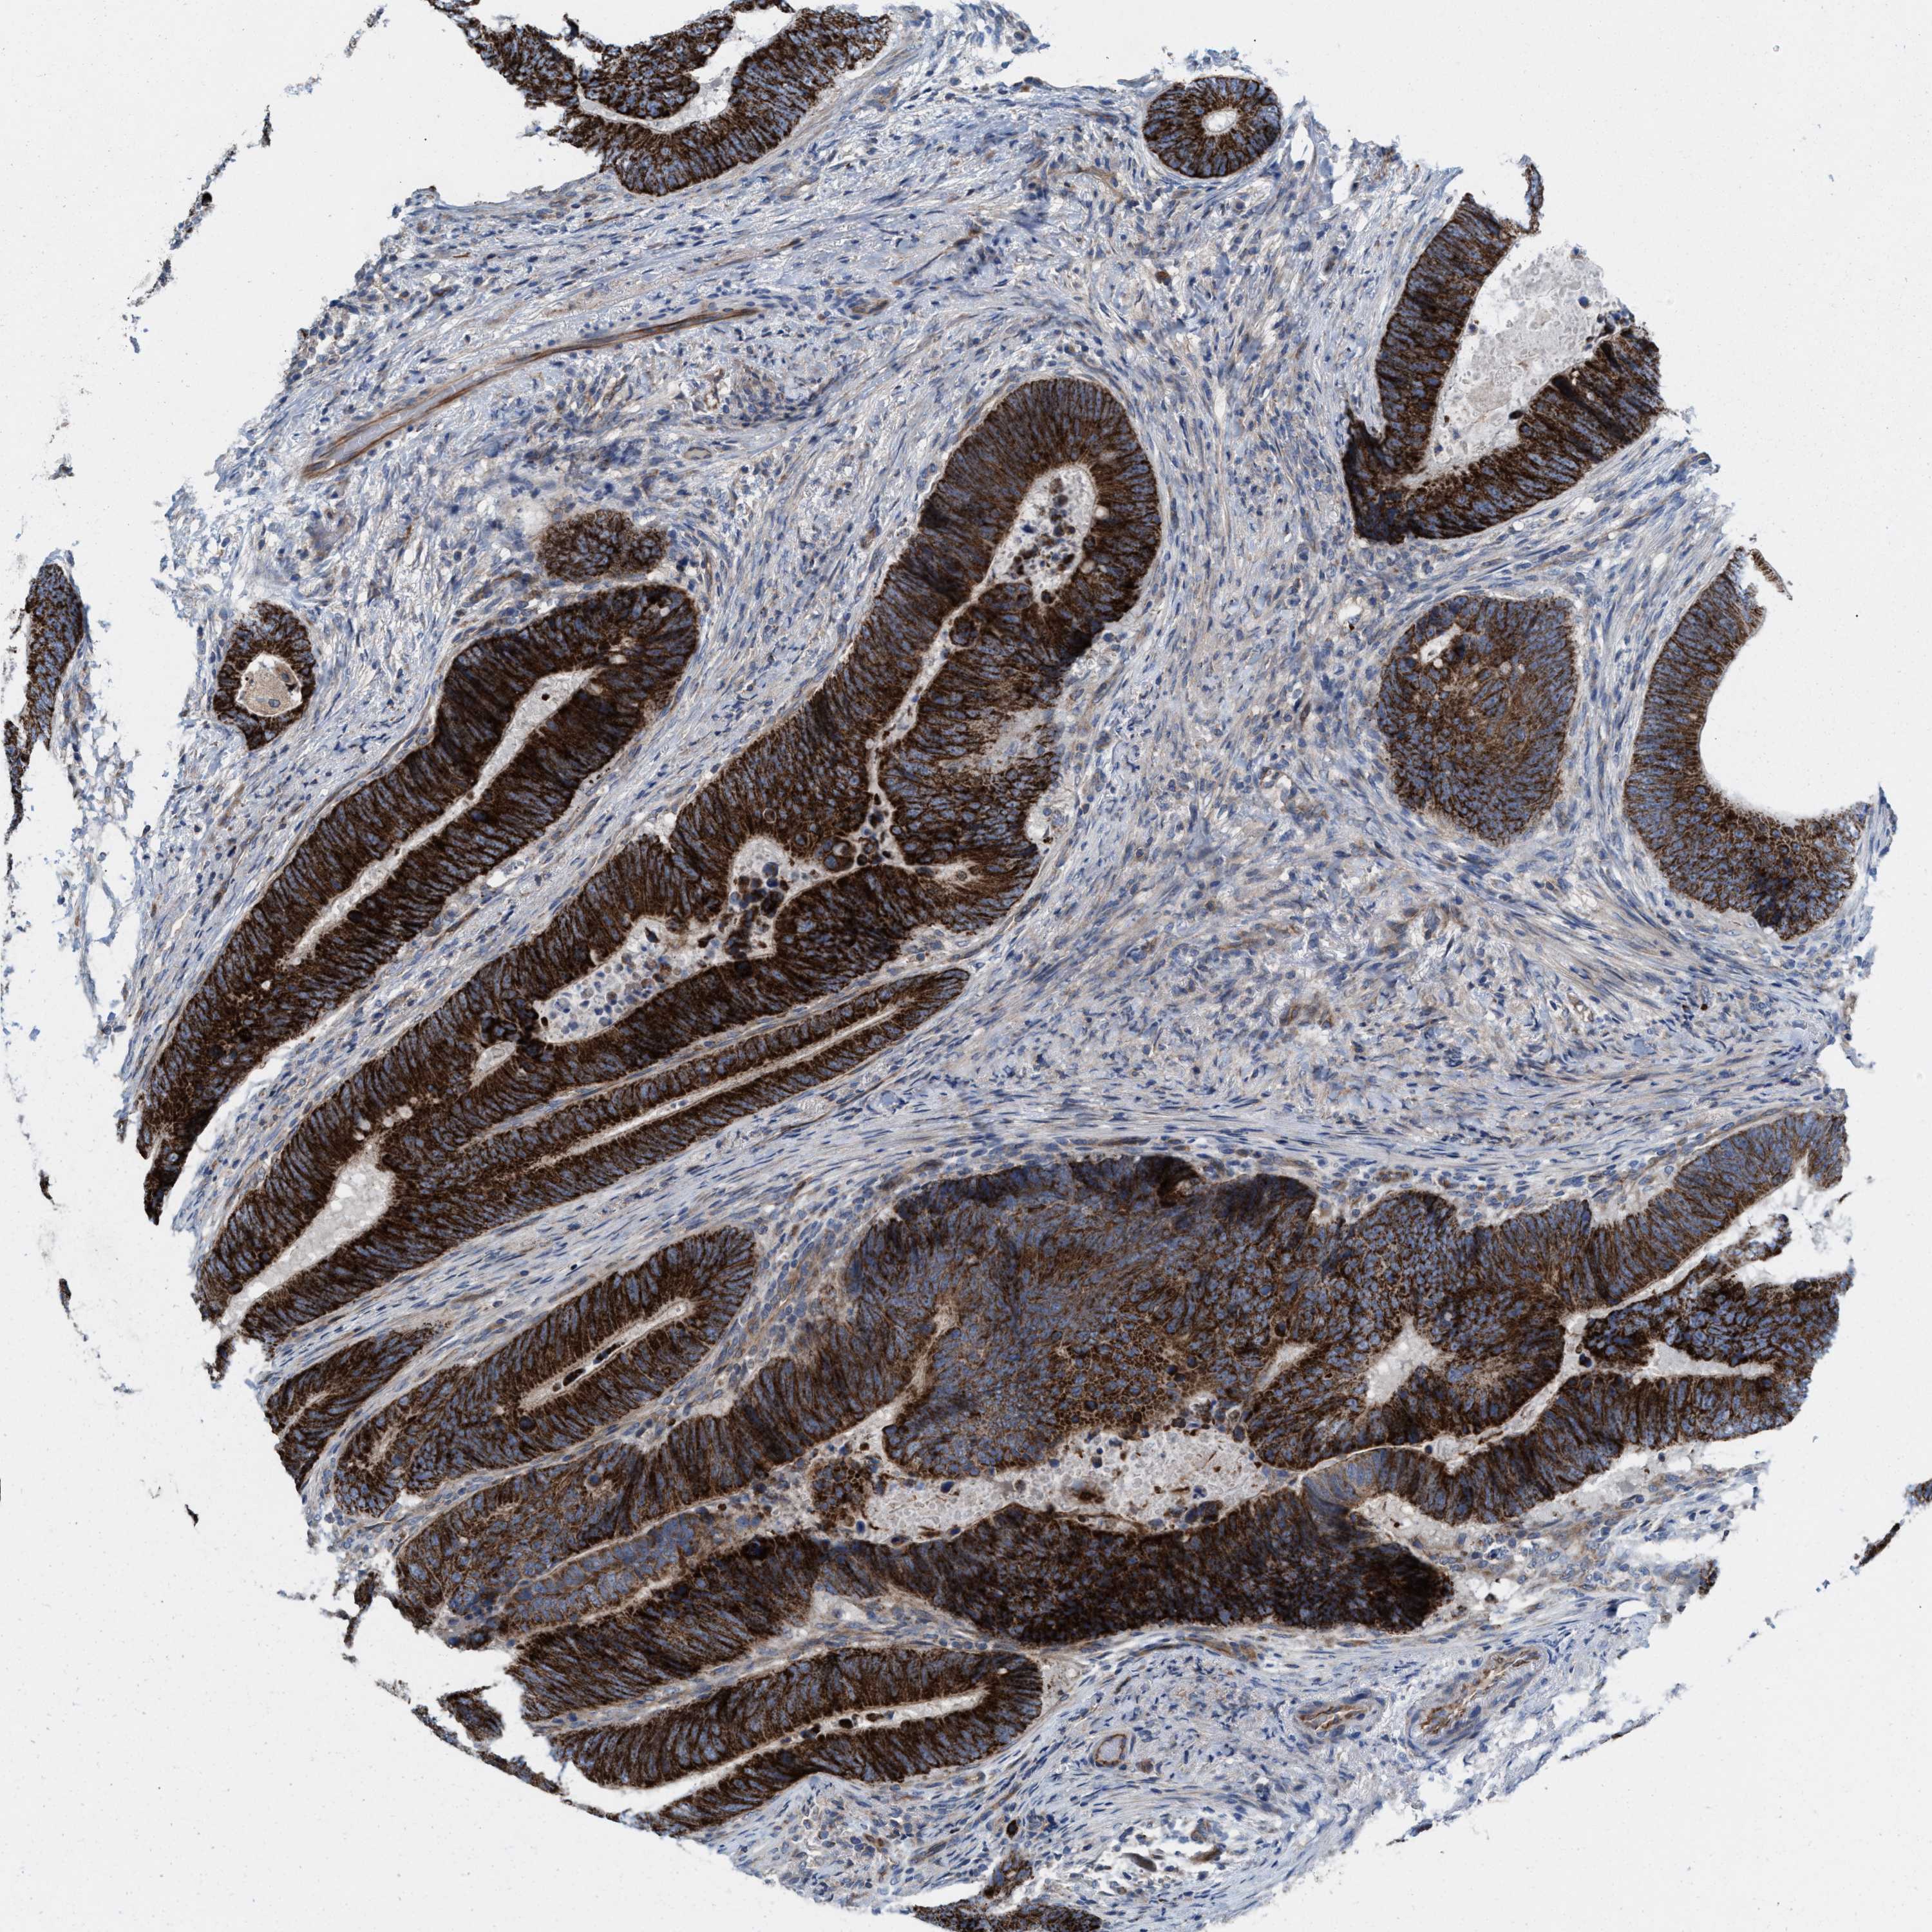

CANCER COLORECTAL CANCER Show tissue menu

Colorectal cancer

Human cancer

Colon adenocarcinoma